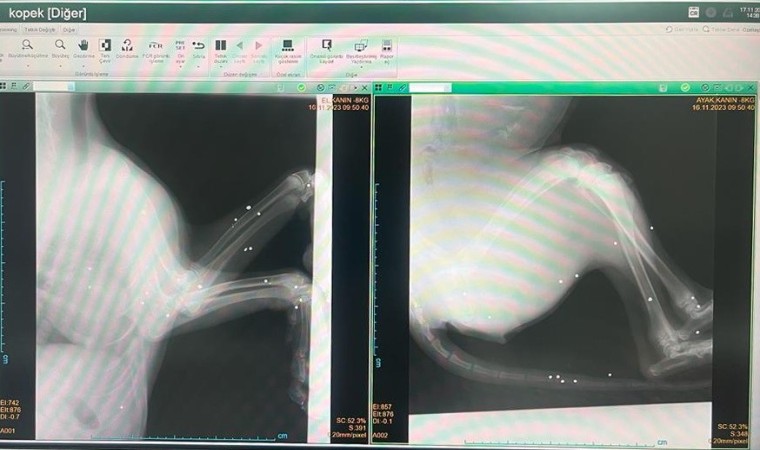

Edinilen bilgilere göre, Adıyaman merkez Ataköy Köyü civarında yerde kanlar içerisinde yatan bir köpeği fark eden vatandaşlar yaralı köpeği araçlarıyla Adıyaman Belediyesi Veteriner İşleri Müdürlüğüne getirdi. Burada tedavi altına alınan köpeğin çekilen röntgen filmlerinde 22 adet saçma tespit edildi.

Adıyaman Belediyesi Veteriner İşleri Müdürü Veteriner Hekim Yusuf Işık tarafından tedavisi devam ettirilen ve kimliği belirsiz şahıs yada şahıslar tarafından av tüfeğiyle vurulduğu öğrenilen köpeğin sağlık durumunun ciddiyetini koruduğu öğrenildi.